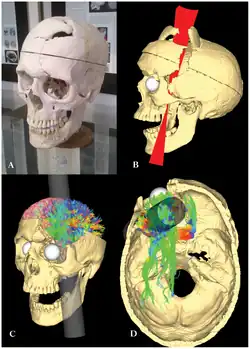

Estudos mais recentes, de Franz Gall e Paul Broca, no século XIX EC, associavam regiões do cérebro como responsáveis por determinadas funções mentais; havendo algum dano, haveria algum tipo de sintomatologia.[9] Um caso histórico emblemático das relações entre lesão cerebral e a alteração das funções cognitivas foi o de Phineas P. Gage. Aos 25 anos de idade, era funcionário de construção de ferrovias da Rutland & Burlington. Um acidente com explosivos, que tinha tudo para tê-lo matado, lançou uma barra de ferro que atravessou seu crânio na região frontal, deixando-o cego do olho esquerdo, mas vivo. Sempre dedicado, bom trabalhador e capaz, Gage teve severas alterações de comportamento após este acidente. Tornou-se displicente, arruaceiro e briguento, passando a ter um comportamento totalmente diferente. A literatura sugere que ele passou a ter estas alterações duradouras em seu comportamento devido às lesões, que alteraram o funcionamento do seu cérebro.[10] O caso de Gage é emblemático na neuropsicologia, pois mostra as relações entre lesão cerebral e as funções cognitivas e motoras. A mudança do comportamento de Gage é atribuído à extensa lesão no lobo frontal, uma das regiões que regulam o controle dos impulsos. Lesões nesta área podem levar a um comportamento egoísta e anti-social.